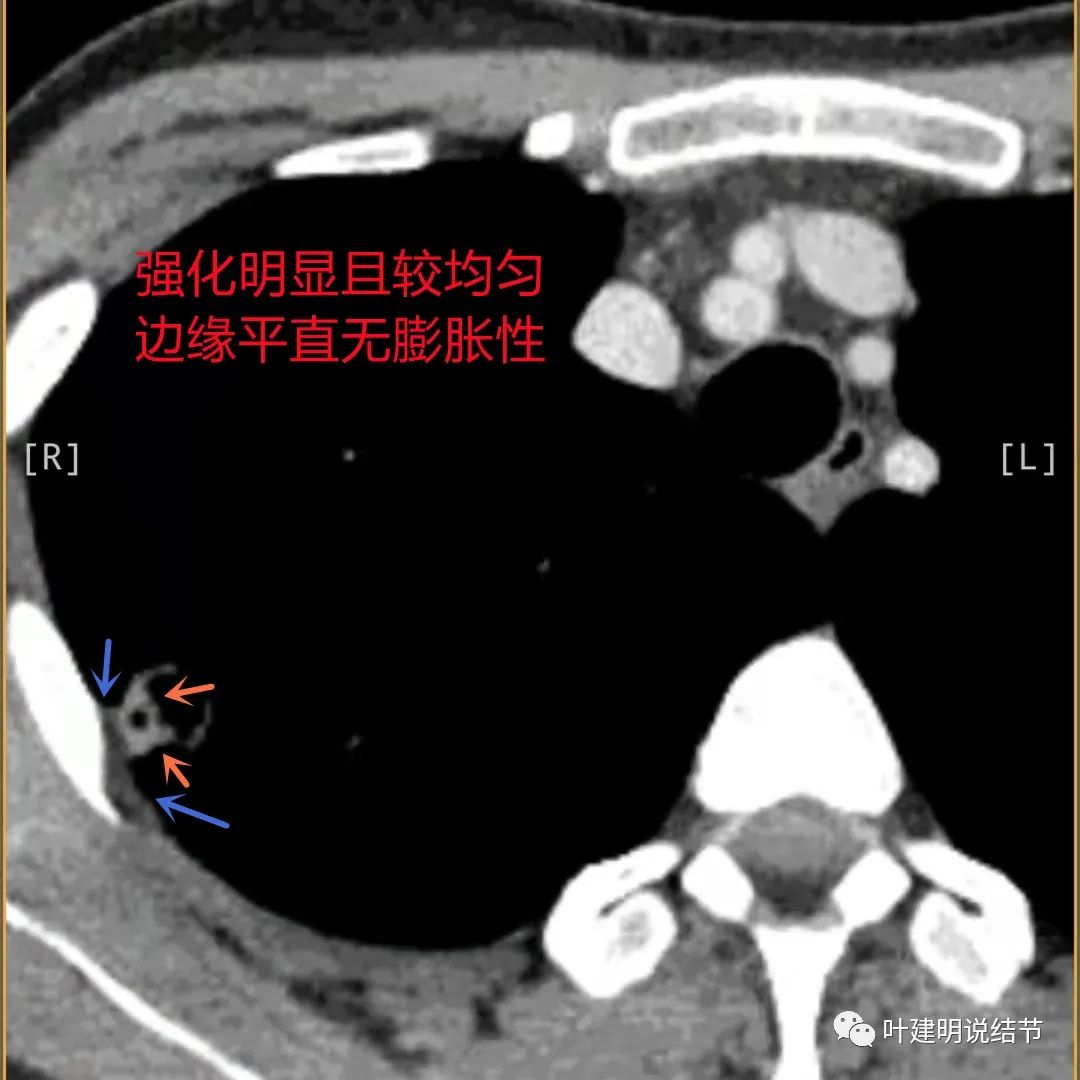

病灶有明显强化(说明炎性可能性大,如果恶性这样强化,血供丰富,应该倍增速度更快。蓝色箭头示胸膜处低于软组织密度的区域;桔色箭头示病灶边缘平直缺乏膨胀性;黄色箭头示中间的空腔

邻近胸膜处的增厚密度低于肌肉组织,病灶强化明显且均匀